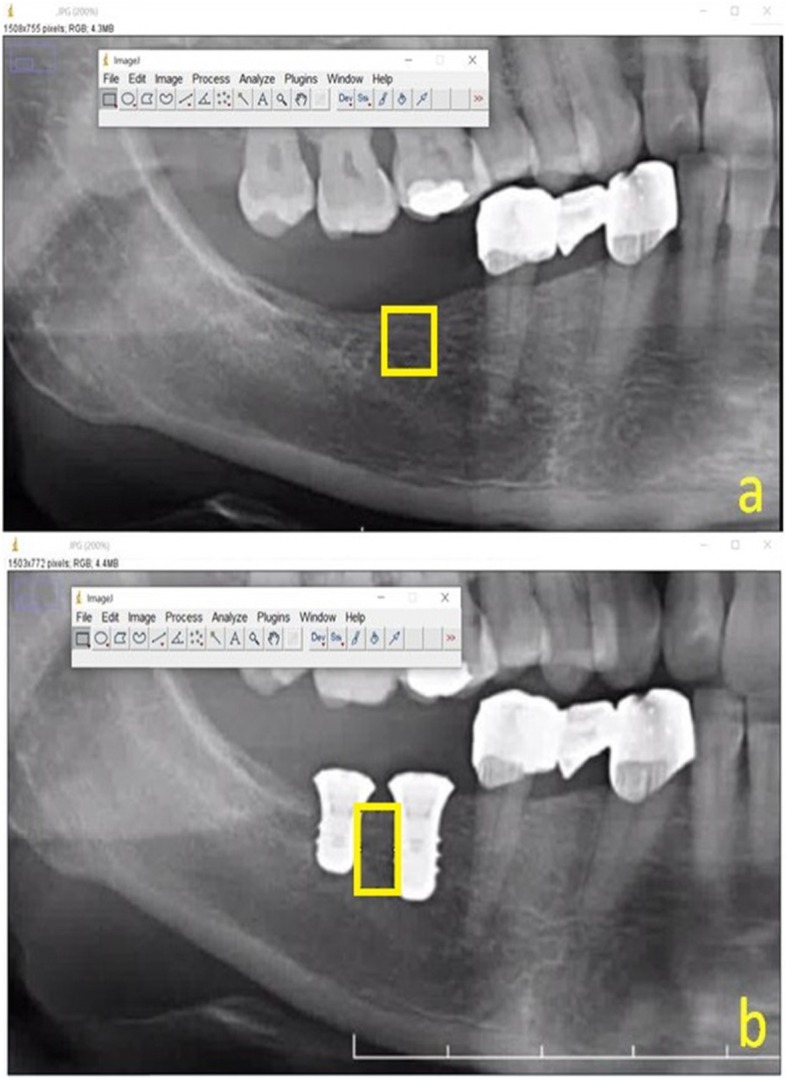

Sixty-seven dental panoramic radiographs (DPRs) were evaluated. All DPRs were obtained with the same radiography device (OP200 D; Instrumentarium Dental, Tuusula, Finland; radiography parameters, 66–85 kVp, 10–16 mA, 14.1 s exposure time). Patients were positioned for radiography according to the manufacturer’s recommendations; the Frankfort horizontal plane was parallel to the floor and the sagittal plane was aligned with the vertical line of the device. The region of interest (ROI) was arbitrarily selected on each radiograph (Fig. 2).

Fig. 2.

Region of interests (ROIs) were selected arbitrarily in a preoperative radiographic image and b a follow-up radiographic image